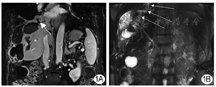

患者男性,76岁。糖尿病10余年。2015年6月11日行肝脏磁共振成像示肝脏多发占位,诊断为原发性肝细胞癌。2015年6月30日行肝细胞癌射频消融(radiofrequency ablation,RFA)+放射性粒子植入术,恢复较好。2018年12月10日因"发现肝细胞癌复发1周"于山东大学附属威海市立医院住院治疗,病变位于肝脏IIIV段,多发,最大直径超过5 cm,靠近膈肌,行肝动脉化疗栓塞术+2次微波消融(microwave ablation,MWA),复查上腹部MR提示肝细胞癌病灶得到控制。2019年7月29日复查MR提示肝细胞癌第2次复发,再次行超声引导MWA,设定功率为60 W,重叠消融作用总时间20 min,术后恢复较好,复查上腹部MR提示肝细胞癌病灶得到控制。2019年9月16日因"乏力、咳嗽1周,发热1 d"再次入住山东大学附属威海市立医院,咳大量金黄色泡沫痰,夜间卧位明显。血常规示:白细胞11.7×109/L,中性粒细胞百分比87%。丙氨酸氨基转移酶45 U/L,转肽酶88 U/L,碱性磷酸酶156 U/L,总胆红素68 mol/L,直接胆红素49 mol/L,白蛋白32.1 g/L,凝血酶原时间15.6 s。血培养、痰培养示肺炎克雷伯杆菌阳性,胸部增强CT提示右肺下叶感染性病变。气管镜提示右肺支气管黏膜炎症改变。胃镜检查提示非萎缩性胃炎伴胆汁反流。上腹部MR+磁共振胆胰管造影(magnetic resonance cholangiopancreatography,MRCP)提示肝脓肿形成并膈肌破坏、肺部感染(图1)。给予哌拉西林他唑巴坦抗感染治疗后患者咳嗽未减轻,复查腹部CT提示肝脏消融区域脓肿形成,于2019年9月30日和10月3日分别行超声引导经皮穿刺肝脓肿引流术,术后引出脓液及浑浊胆汁样液体,但咳嗽无明显缓解。患者黄疸加重,2019年10月转入山东大学齐鲁医院再次行肝内、膈下脓肿穿刺引流术,引流术后CT表现见图2。患者术后黄疸,咳嗽减轻,感染好转。痰液经实验室生化检验证实具有胆汁酸、胆红素等胆汁成分。将5 ml亚甲蓝溶液通过引流管注入,然后从口腔中咳出含有亚甲蓝的痰液,间接证实了胆管支气管瘘(bronchobiliary fistula,BBF)。2020年1月复查CT提示肝细胞癌复发,肝门部、腹膜后淋巴结转移,患者感染、黄疸加重,不适合外科手术,于2020年1月死亡。

BBF的典型症状为胆汁样痰,但早期诊断困难。本例患者每日咳嗽大量金黄色痰液,夜间卧位明显,笔者起初误以为是胃食管反流病引起吸入性肺炎导致的脓痰。随后化验痰中含有胆汁成分,将亚甲蓝溶液通过引流导管注入后从口腔咳出,间接提示可能存在BBF。MR+MRCP的优势在于可显示大胆管及扩张的胆管,也可显示局限性的支气管积液征[4]。本例患者行MR+MRCP提示膈肌损伤并脓肿形成,冠状位MR图像及MRCP考虑膈肌破损、脓肿与肺部相通,结合患者症状及痰液化验,证实BBF。经皮肝穿刺胆管造影术或内镜逆行胰胆管造影术可显示胆道与支气管之间的瘘管异常,这通常是BBF的最直接证据,但本病例未获得此证据[5]。另外,SPECT/CT检查和腔内超声造影检查也可以较好地显示BBF[6]。